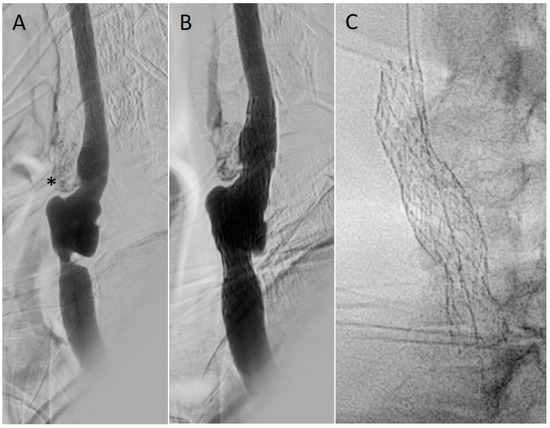

Infective Endocarditis and Complications; Surgical Indications and Management: An Integrative Review

Infective endocarditis (IE) is an infection of the endocardial surface of the heart involving native or prosthetic valves, endocardial structures, or intracardiac devices/leads. Unfortunately, incidence has risen in many settings over recent years. Historically, the incidence has been about 3–10 cases for every [...] Read more.

Infective endocarditis (IE) is an infection of the endocardial surface of the heart involving native or prosthetic valves, endocardial structures, or intracardiac devices/leads. Unfortunately, incidence has risen in many settings over recent years. Historically, the incidence has been about 3–10 cases for every 100,000 person-years and was elevated to about 13.8 cases per 100,000 person-years in 2019. Despite advancements in both detection and treatment, mortality remains high, seen with inpatient mortality rates of 18%, along with a 6-month mortality rate of 30%. IE can be a fatal condition if left untreated, in part due to the multiple serious complications that can arise. By anticipating certain complications, clinicians can be better prepared to treat patients with this condition. This article provides an integrative review of the potential complications of IE. These complications vary depending on whether the patient has native or prosthetic valves. There are cardiac, embolic, and immune-complex mediated complications that can occur. Ultimately, IE can lead to multiorgan dysfunction and result in septic shock and disseminated intravascular coagulopathy (DIC). While the mainstay of treatment for IE remains medical, certain cases require surgical intervention. Due to their close relationship, a review of the indications for surgery in the treatment of IE is also presented in this article. By having a general scope of the complications of IE and when to get a surgical consult, clinicians can be better equipped to care for patients with a potentially fatal condition that is becoming increasingly more frequent. Full article

Figure 1